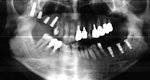

普通、歯科医院で撮影している「レントゲン写真パノラマ」というのがこのような写真です。

横面から撮影していますので、平面しか見ることはできません。

では、CTで撮影したものがどう見えるのかご覧下さい。

まだまだ、神経や血管の位置がよくわかりません。